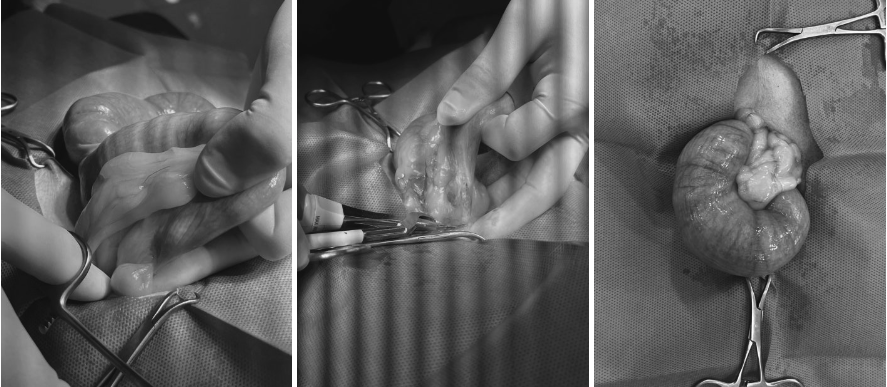

제거된 자궁 사진/ 출처: 라온동물메디컬센터

염증이 심한 자궁은 매우 취약하기 때문에 수술 중 파열 위험을 최소화하며, 주변 조직 손상을 줄이는 방향으로 신중하게 수술을완료하였습니다.